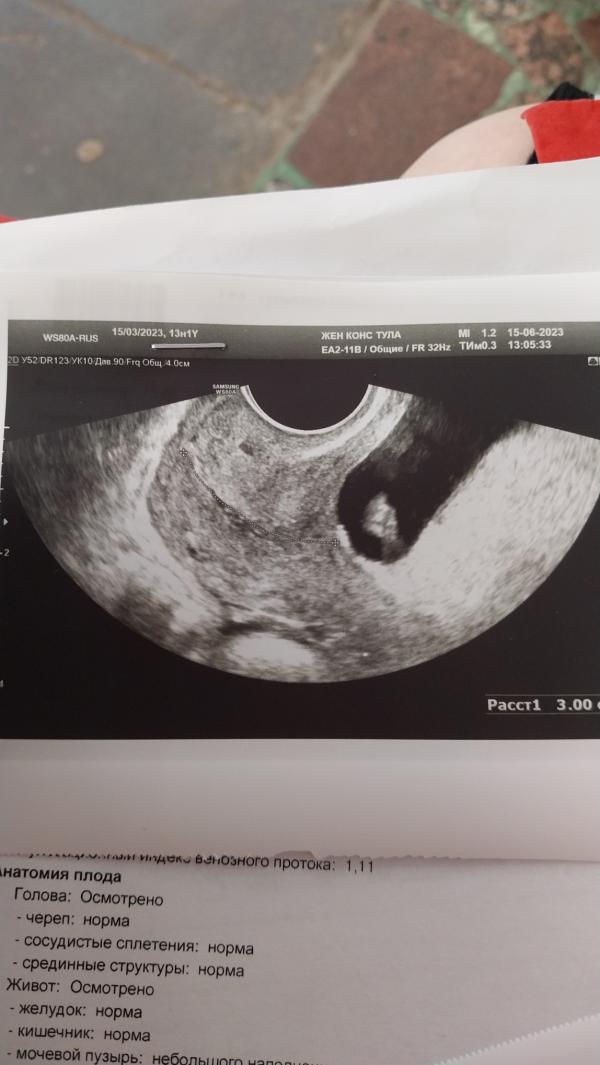

Девочки, периодами одолевает паника. Малышка очень странно лежит в матке. Толчки и шевелюшки уже чувствую. Но, похоже, что она уже 3 дня как отвернулась к позвоночнику и чувствую я ее очень редко, в основном когда ложусь на бок. Доплером сердечко хорошо прослушивается, но практически над лонным сочленением. Это вообще нормально? И может, если это вообще нужно, как-то повлиять на ее расплложение?

Сходите на УЗИ, если сильно переживаете. Но лично я не вижу вообще поводов для волнения. Сердечко слышно, малыш шевелится. У вас ещё такой срок, когда ребенок там может вертеться как ему вздумается